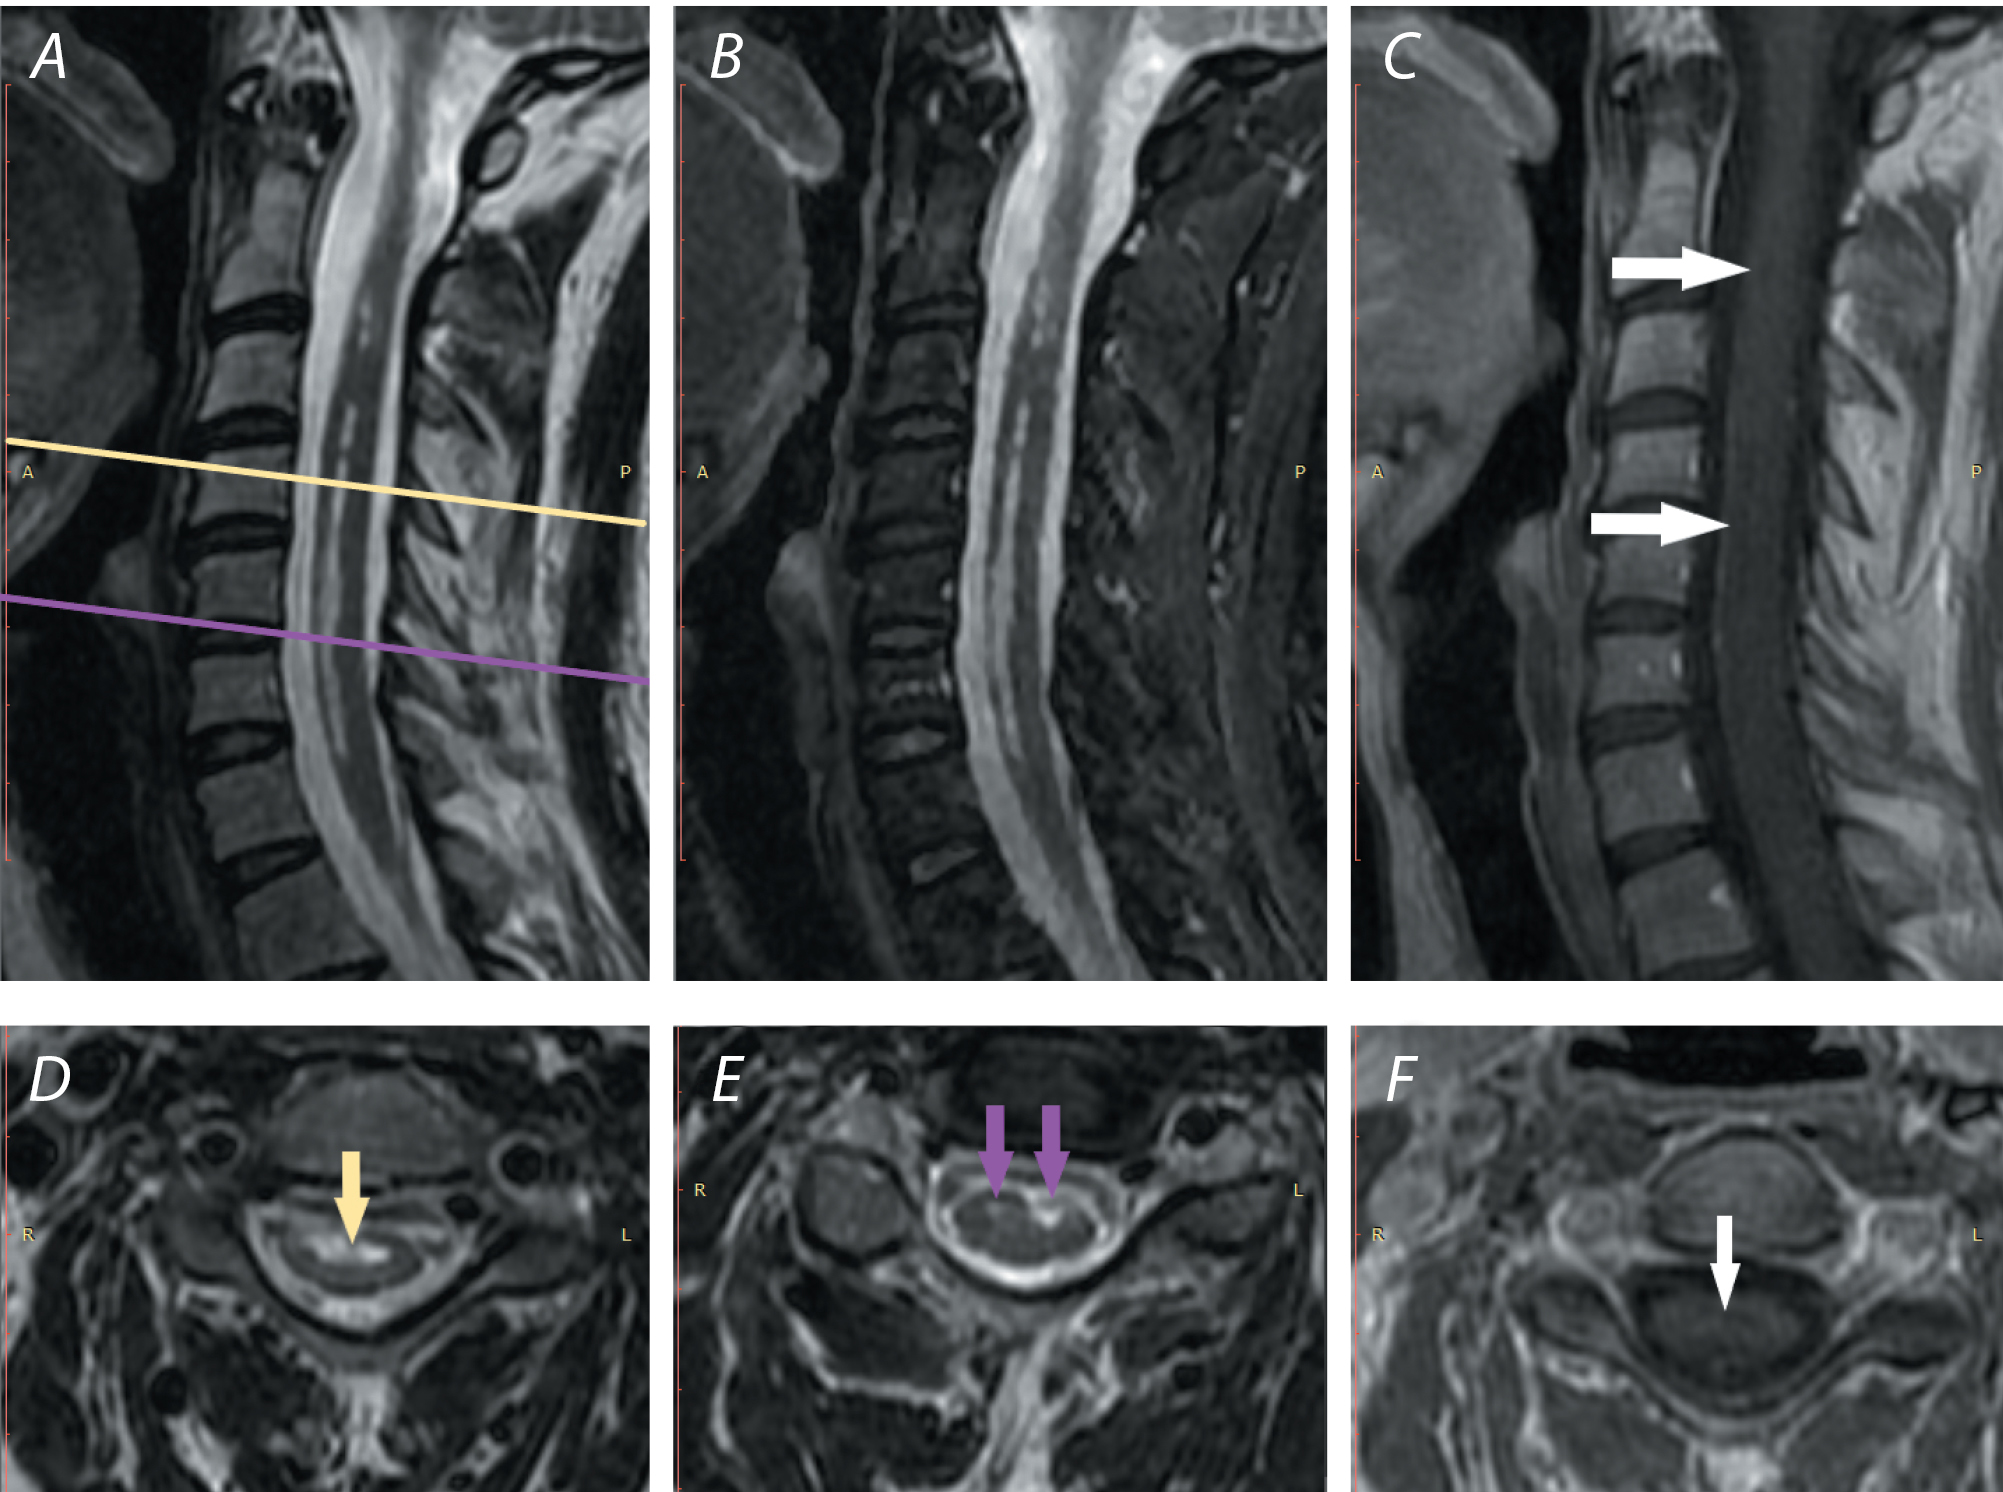

Для ДВИ СМ применяется однократная эхопланарная визуализация с максимальным коэффициентом b 600–1000 с/мм2 и толщиной среза 3 мм. Измеряемый коэффициент диффузии, регистрируемый у пациентов с ИСИ, колеблется от 0,23 до 0,9 × 103 мм2/с (рис. 1) [23].

Рис. 1. МР-исследование пациента П. с инфарктом СМ на уровне Тh11–Th12.

А — Т2-ВИ, сагиттальная плоскость: интрамедуллярный гипер-интенсивный очаг вытянутой формы (белые стрелки) на уровне Тh11—Th12;

В — Т2-STIR, сагиттальная плоскость: интрамедуллярный гипер-интенсивный очаг вытянутой формы (белые стрелки) на уровне Тh11–Th12;

C — ДВИ, коронарная плоскость: интрамедуллярный гиперинтенсивный очаг неправильной формы на уровне Тh11–Th12 (белая стрелка), b = 800;

D — Т2-ВИ, аксиальная плоскость: гиперинтенсивный интрамедуллярный очаг справа на уровне Тh11–Th12;

E — ДВИ, аксиальная плоскость: интрамедуллярный гиперинтенсивный очаг справа на уровне Тh11–Th12 (синие стрелки), b = 800;

F — ДВИ, аксиальная плоскость, карта измеряемого коэффициента диффузии: отмечается рестрикция диффузии, соответствующая очагу на ДВИ (синие стрелки), b = 800.

Fig. 1. MR image of patient P. with SC infarction at Th11–Th12.

A) T2-weighted image, sagittal plane: intramedullary hyperintense elongated lesion (white arrows) at Th11–Th12;

В) Т2-STIR, sagittal plane: intramedullary hyperintense elongated lesion (white arrows) at Th11–Th12;

C) DWI, coronal plane: intramedullary hyperintense lesion of irregular shape at Th11–Th12 (white arrow), b = 800;

D) T2-weighted image, axial plane: hyperintense intramedullary lesion at Th11–Th12;

E) DWI, axial plane: intramedullary hyperintense lesion on the right at Th11–Th12 (blue arrows), b = 800;

F) DWI, axial plane, ADC map: diffusion restriction corresponding to the lesion on DWI (blue arrows), b = 800.